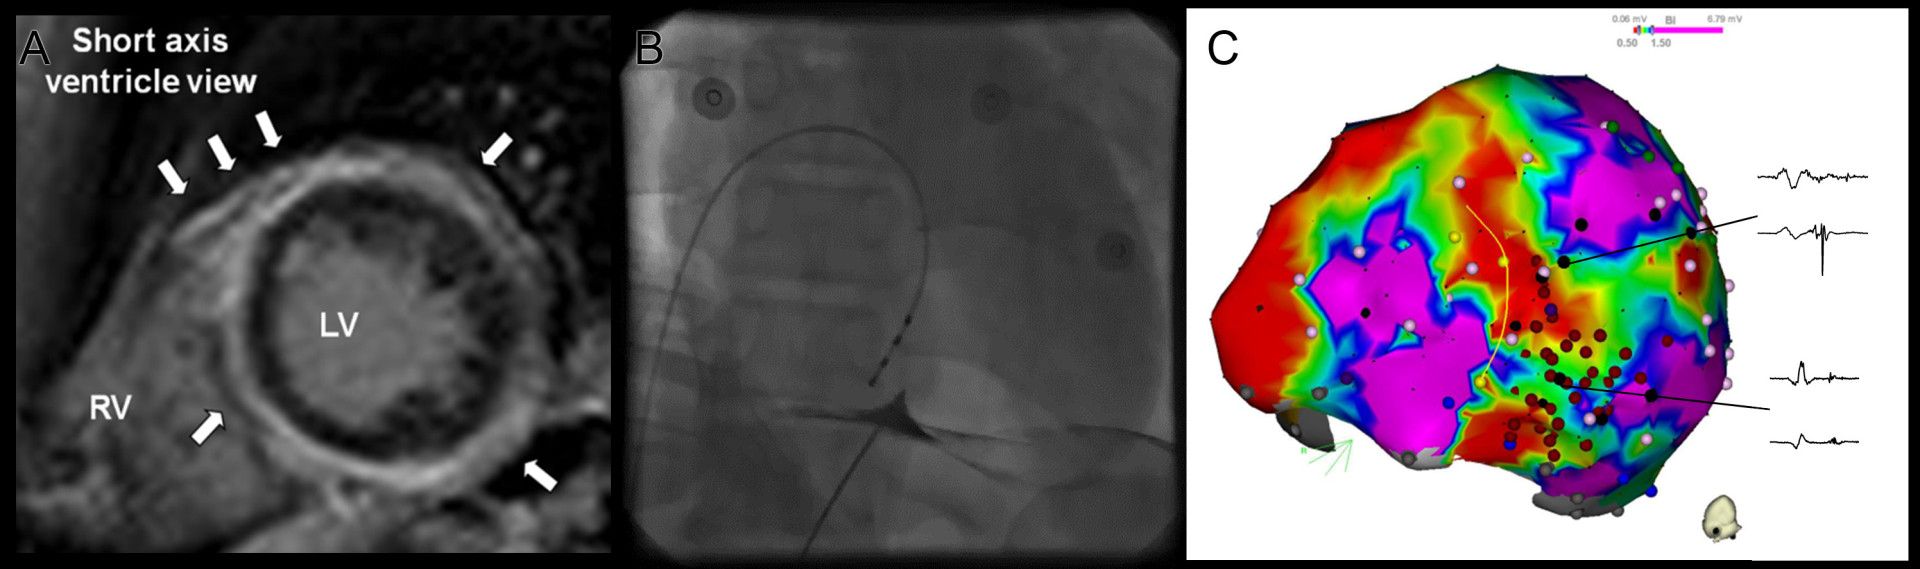

U pacientů se strukturálním postižením srdce je základní metodou prevence NSS implantace ICD a ablace je indikována v případě symptomatických KT, které vedou k intervencím ICD (obr. 2). Část pacientů může mít polymorfní KA, které nemají stabilní okruh reentry, ale jsou spouštěny časnými komorovými extrasystolami (KES). Je prokázáno, že úspěšná eliminace spouštěcí ektopie katetrizační ablací může účinně zabránit i recidivám polymorfních KT.29 Stejně tak doporučené postupy doporučují katetrizační ablaci jako metodu léčby u pacientů s monomorfními KT u pacientů po chirurgické korekci Fallotovy tetralogie.

Obr. 2 Příklad epikardiálního mapování a ablace u pacienta s mutací desmoplakinu a neischemickou kardiomyopatií. Panel A znázorňuje obraz z magnetické rezonance s pozdním sycením gadoliniem lokalizovaným dominantně epikardiálně. Endokard není postižen. Panel B ukazuje punkci epikardiálního prostoru pomocí perkutánního subxiphoidního přístupu. Parietální perikard je označen malým množstvím kontrastní látky. Panel C zobrazuje elektroanatomickou voltážovou mapu z inferiorního pohledu. Oblasti s pomalým vedením vzruchu (tzv. pozdní potenciály) byly modifikovány pomocí radiofrekvenční ablace (červené tečky). To vedlo k potlačení inducibility komorových tachykardií.